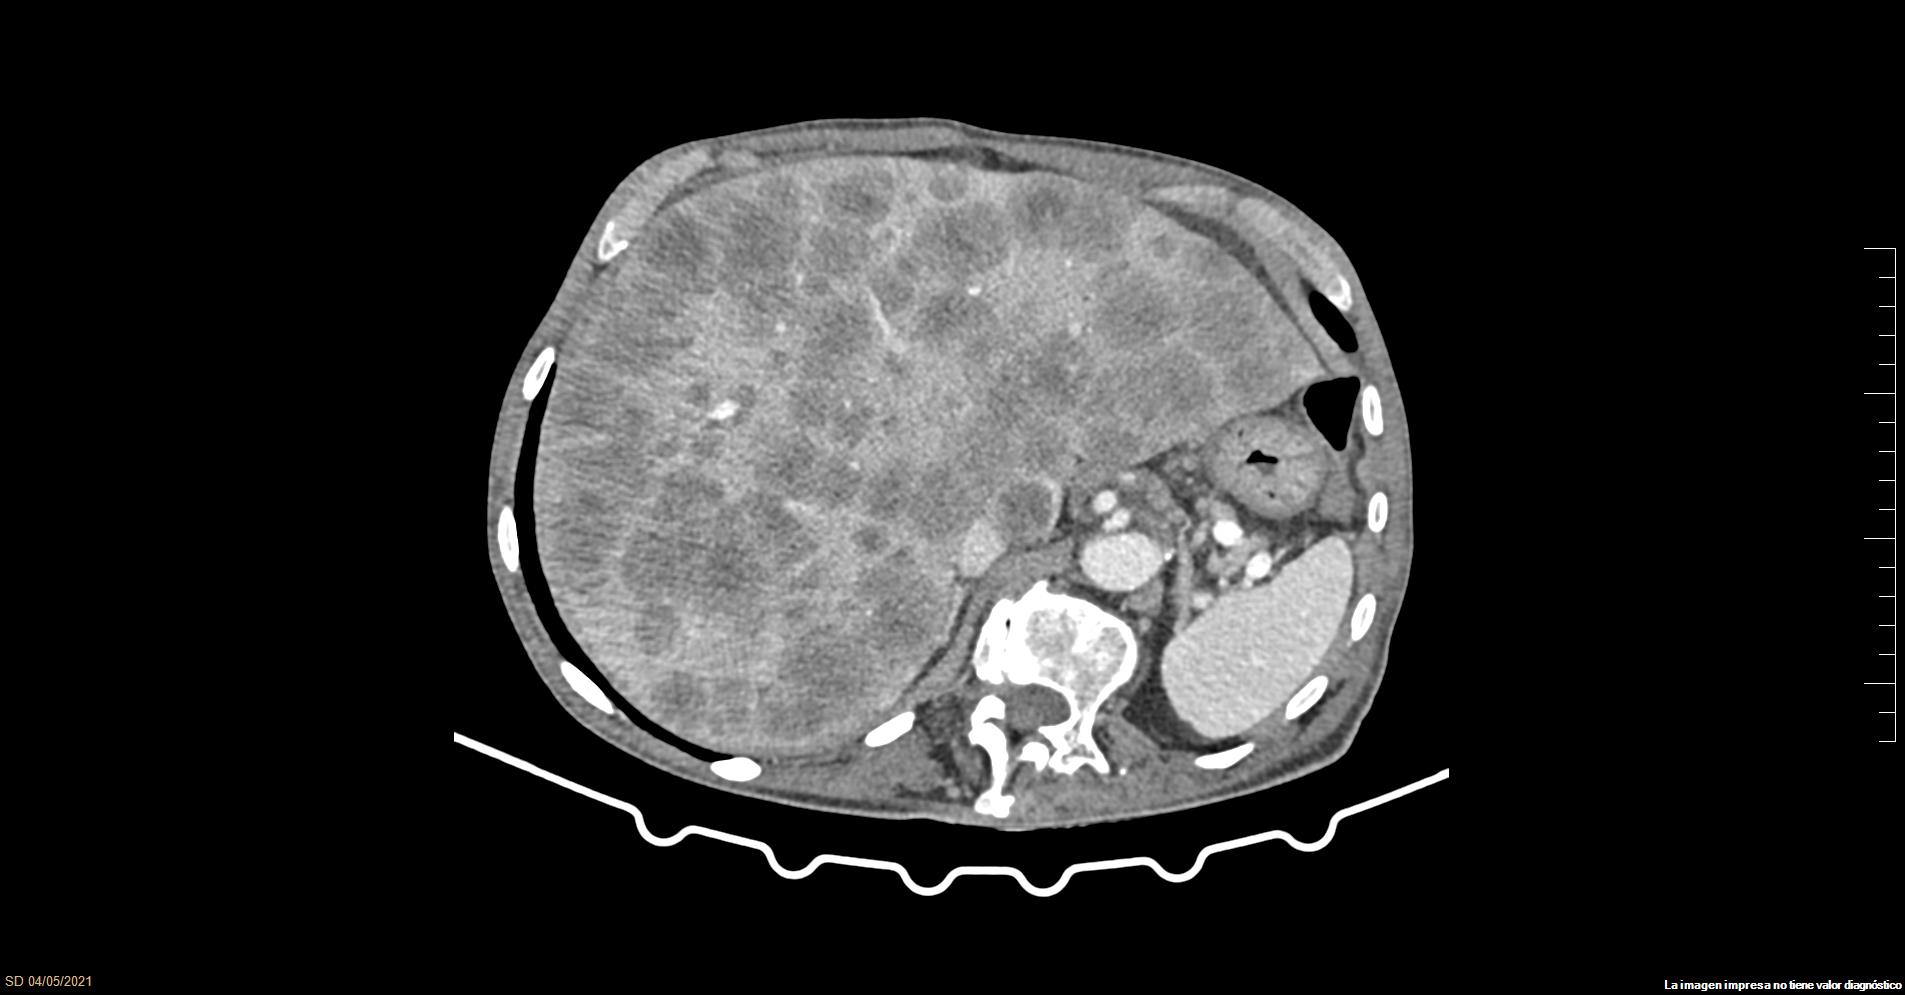

TAC abdominal: lesiones nodulares en el parénquima hepático de apariencia tumoral, así como hepatomegalia.

• Juicio clínico: Hepatocarcinoma vs nódulos metastásicos.

• Diagnóstico diferencial, concordancia con el hospital (en su caso): Nódulos de regeneración, hepatocarcinoma, metástasis, nódulos displásicos, cirrosis, hepatitis